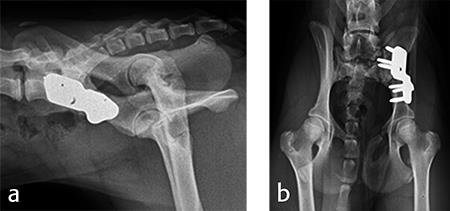

A 4-month-old female boxer puppy weighing 15.0 kg presented with bilateral hind limb weakness and reluctance to walk. Physical examination revealed bilateral hip instability (positive Ortolani sign) and severe pain on full extension of the hips. The neurological exam was normal. The radiographs revealed bilateral hip subluxation and a distraction index of 0.65 of the right hip and 0.6 of the left hip (Fig 7). Very mild osteoarthritis was seen and femoral head coverage by the dorsal acetabular rim was good (Fig 8). Angles of subluxation (10° R and 20° L) and reduction (30° R and 40° L) of the hips were measured under anesthesia.

For each surgical procedure, the patient was placed in dorsal recumbency to enable the pubic ostectomy. The patient was repositioned in lateral recumbency to perform the DPO. A left ilial osteotomy was performed caudal to the sacrum. A 25° DPO/TPO plate was attached to the caudal ilial segment using locking 3.5 mm screws in the three stacked combi holes. The caudal acetabular segment was rotated laterally until the cranial aspect of the plate was in contact with the lateral aspect of the cranial ilial segment. The osteotomy site was compressed and the plate was secured to the cranial ilial bone segment using a 3.5 mm cortical screw in the LCP combi hole in the cranial side of the plate. Three additional 3.5 mm locking screws were placed in the remaining stacked combi holes in the cranial segment of the plate (Fig 9).